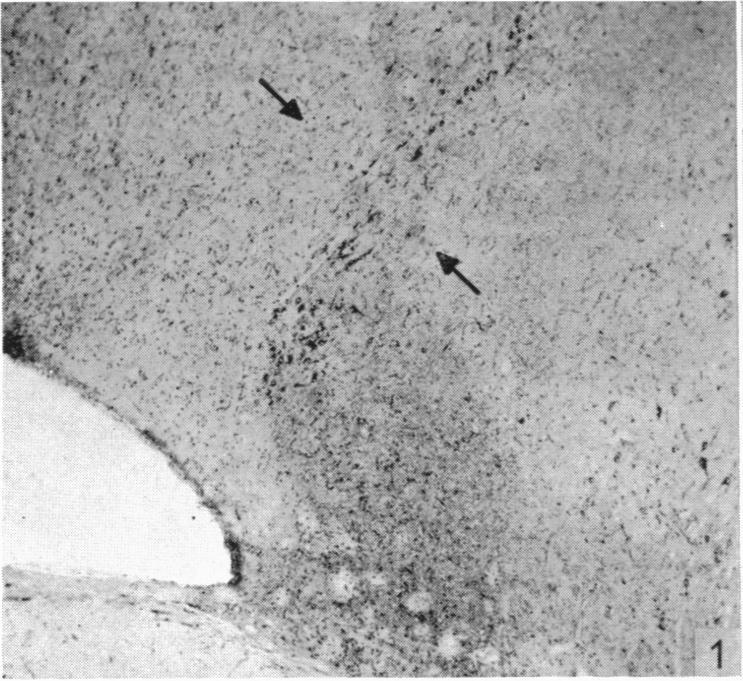

Hypothalamic neurosecretion in the dog and cat, with particular reference to the identification of neurosecretory material with posterior lobe hormone.

J Anat. 1955 Jul;89(3):301-16.